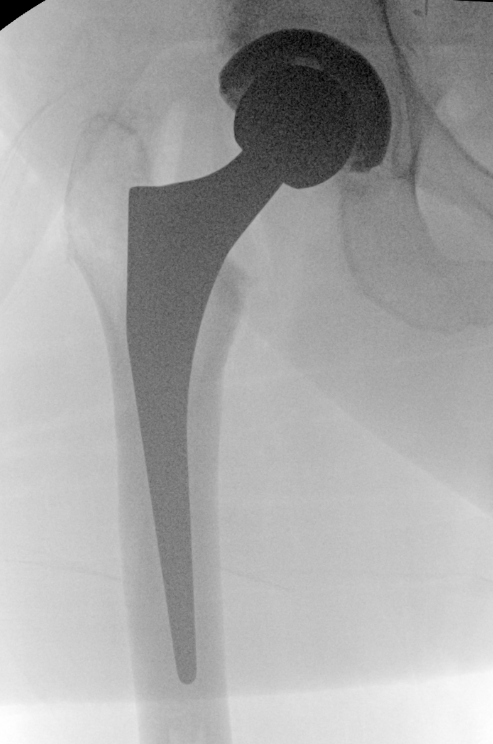

Postoperative LLD

Incidence

Transient perception of LLD common

- usually apparent leg lengthening

Cause

- leg was slightly short, now normal length

- contracture releases

Typically resolves over 6 months

Management

Nonoperative

Delay using shoe lift for 6/12

- allows apparent LLD to resolve

Shoe insert for opposite leg

Operative

- 21 cases of LLD mean 4 cm following THA

- treated with revision

- LLD restored to within 1 cm in all cases